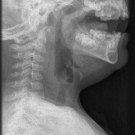

Nicholas V. Mendez, BS; Ayman M. Salah, PhD; Kelsey A. Musgrove, BS; Syed A.A. Rizvi, PhD, MBA; Sultan S. Ahmed, MD; Jasmin Ahmed, BS, MS, MD

​A 33-year-old woman with no significant past medical history presented to our family medicine practice with concern for a headache when she laughs or leans her head forward.

10/29/2019